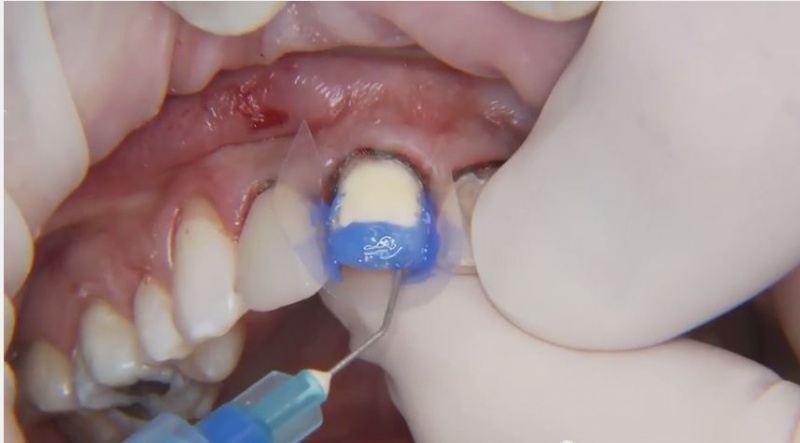

- Clinical: Anesthetic Delivery

- Clinical: Cementing Veneers